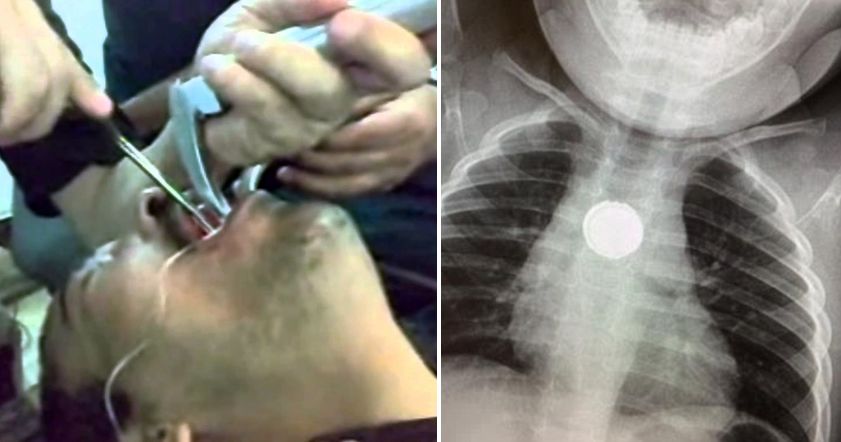

Юмор//5 Окт, 2018 Турист украл и проглотил дорогое кольцо, из-за чего оказался в больнице Турист из Ирландии украл кольцо за 40 224 долларов США и проглотил его, испугавшись полиции.